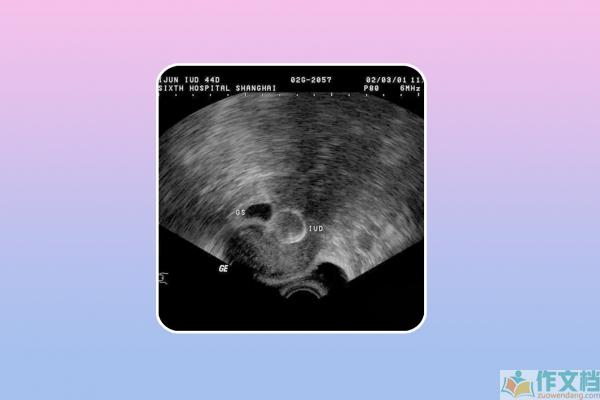

在进行无痛人流手术之前,医生会对患者进行一系列的检查,包括妇科检查、B超检查、血常规、凝血功能、心电图等。这些检查的目的是了解患者的身体状况,确定怀孕的时间和位置,排除手术的禁忌。